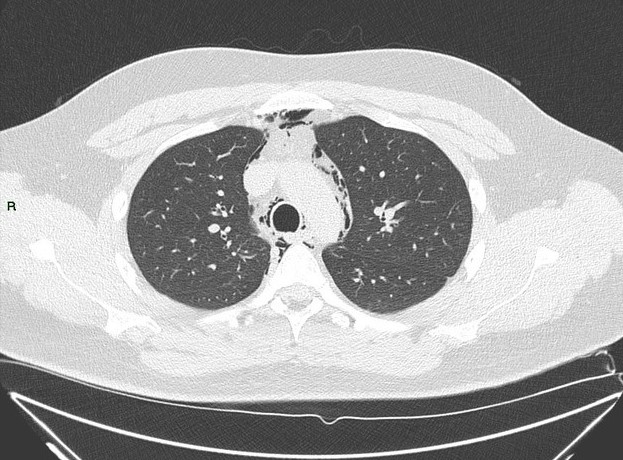

Tràn khí trung thất

Tràn khí trung thất - Ảnh 4

» Thông tin: Nam giới – 25 tuổi.

» Lâm sàng: Đau ngực.